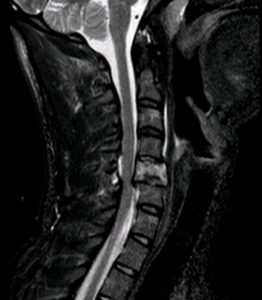

Accidente tráfico. Politrauma. Fractura cervical C5 inestable con compresión medular

Se realizó corpectomía C5 con reconstrucción anterior en un primer tiempo (prótesis expansible + placa cervical). En el mismo acto, se dio la vuelta al paciente y se realizó una fijación posterior para asegurar el montaje (dadas las lesiones ligamentosas asociadas).